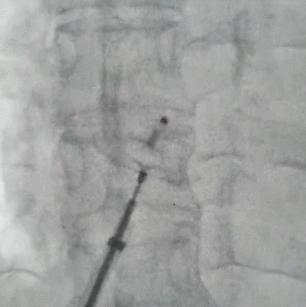

卵圆孔未闭的治疗并不复杂,穿刺大腿根部的股静脉插入心导管,将封堵器送到未闭卵圆孔,就可达到治愈目的。手术过程简单、安全、可靠,并发症罕见,整个手术过程仅需 20-30 分钟。术后第一天可下床活动。术后 3~6 个月内皮组织就完全覆盖封堵器。与冠心病不同,一般术后不需要长期服药,仅服用阿司匹林6个月,术后应定期复查心脏超声及右心声学造影。